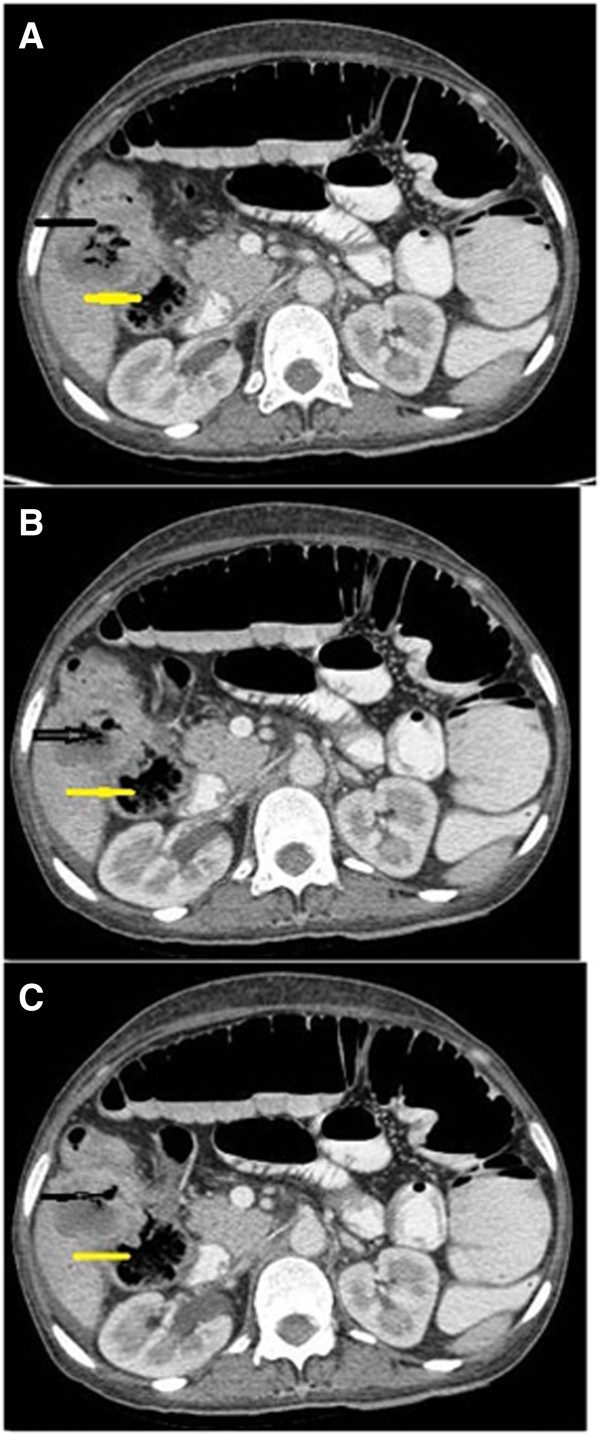

A NCCT abdomen showing mild thickening of wall of hepatic flexure What Is Malignant Neoplasm Of Hepatic Flexure A large bowel stricture with shouldering at the hepatic. — hepatocellular carcinoma (hcc) is the most common type of primary liver cancer. Mendelson, md september 21, 2024. The hepatic flexure is the bend. — chronic infection with the hepatitis b virus (hbv) or hepatitis c virus (hcv) increases your risk of liver cancer. hepatic flexure cancers are. What Is Malignant Neoplasm Of Hepatic Flexure.

From www.researchgate.net